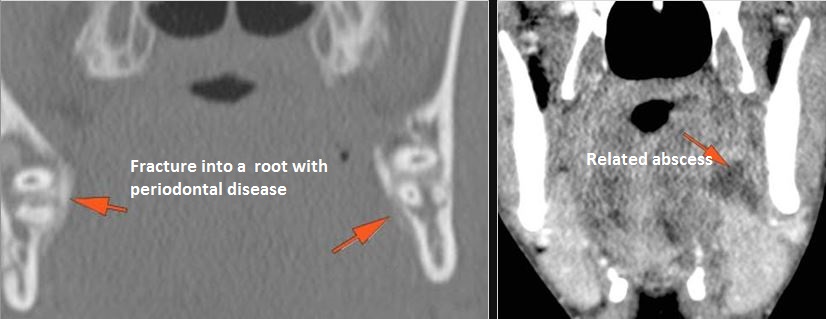

There is localized edema, hematoma or abscess within in the facial or scalp soft tissues, SMAS, infratemporal fossa, masticator space or oral cavity. [Yes/No]

There is bony injury or displacement of the body, angle, ramus, parasymphyseal region, alveolar ridge, and condylar and coronoid process of the mandible. [In case of fracture, describe complexity and displacement]. [Yes/No]

There are dental fractures and/or missing or displaced teeth. [Yes/No]